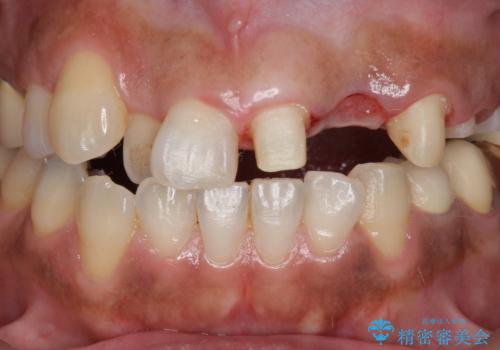

- 左上2番目の歯がグラグラするので診て欲しいといらっしゃった方の症例です。

左上2番目の歯は歯根が破折してため抜歯し、左上123のブリッジによる欠損補綴を行いました。

左上4、5番目の歯は根尖病変を認めたため再根管治療を行い、オールセラミッククラウンによる補綴を行いました。

なお左上4に関しては縁下歯質を改善するため、歯冠挺出を行っております。